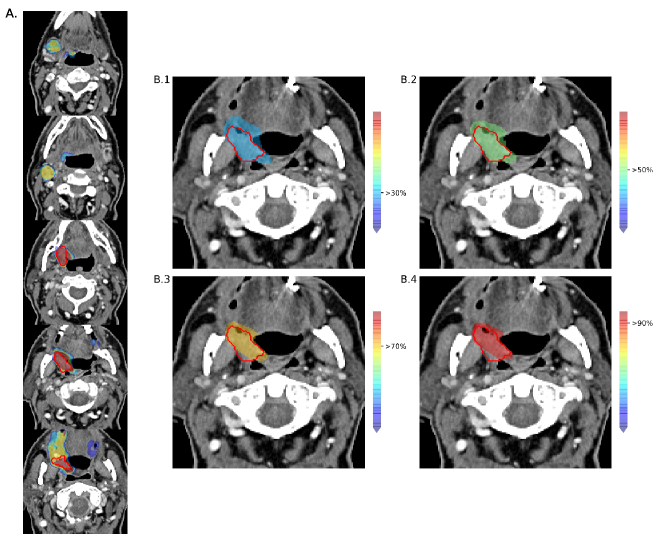

Figure 3: Examples of the output of the proposed method. A. Outcome probabilities displayed on the axial view of slices extracted from the CT 3D volume of a patient in the dataset. The red line represents the GTVp provided as ground truth, while the different colors show different areas of tumor probabilities. B. Four examples of customized outputs based on different probability threshold settings, as shown by the color bars on the right side of the images. In B.1 only the areas containing pixels with tumor probabilities above 30% are displayed, above 50% in B.2, above 70% in B.3 and above 90% in B.4.

In figure 3, we show how the probability map predictions of our network looks on the CT image of a patient. On the left side, the total range of probability is shown on few slices extracted from the axial plane. On the right side, four cases of different probability threshold settings are displayed. The range of probability shown on the image for each case corresponds to the one above the selected threshold up to 100%. Increasing the probability percentage shrinks the predicted area around the tumor.